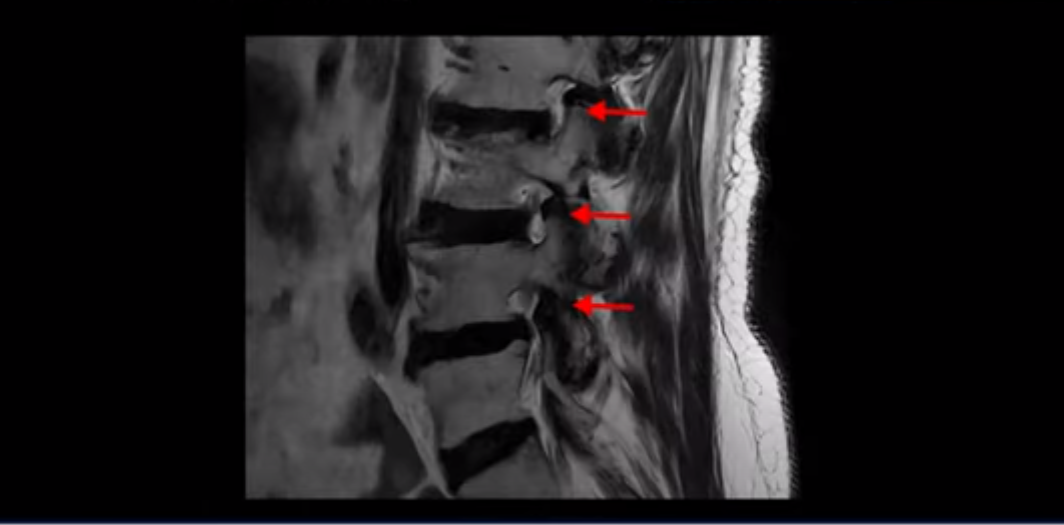

이 환자분은 고관절 쪽이 10년이 넘게 아팠고, 5년 전에는 갑자기 허벅지와 다리가 아파 못 걷게 돼서 허리 수술을 받습니다. 그리고 3년 후에 다시 재발합니다. 고관절 통증은 허리 수술 이후에도 좋아지지 않고 계속 아팠습니다. 수술하고 재발한 이후로 원래부터 아프던 고관절은 물론, 양쪽 엉덩이와 사타구니 및 허벅지가 다 아파서 잘 걷지도 못하고 또 앉거나 누워도 아파서 뒤척거리기도 힘듭니다. 이분 MRI를 보면 여러 마디가 다 안 좋습니다.

2번 3번은 디스크가 심하게 터져있고 협착까지 있습니다.

4번 5번에는 왼쪽으로 이전에 수술한 자국이 보이는데

수술한 부위에 상처 조직이 생겨 유착된 부위가 보입니다. 왼쪽, 오른쪽 신경 가지가 빠져나가는 추간공을 보면 오른쪽도 여러 마디가 좁아져 있고

왼쪽도 여러 마디가 좁아져 있습니다.

이렇게 허리 여러 마디와 신경 나가는 구멍 오른쪽, 왼쪽이 다 안 좋으니까 양쪽 엉덩이와 다리가 다 아픈 겁니다.